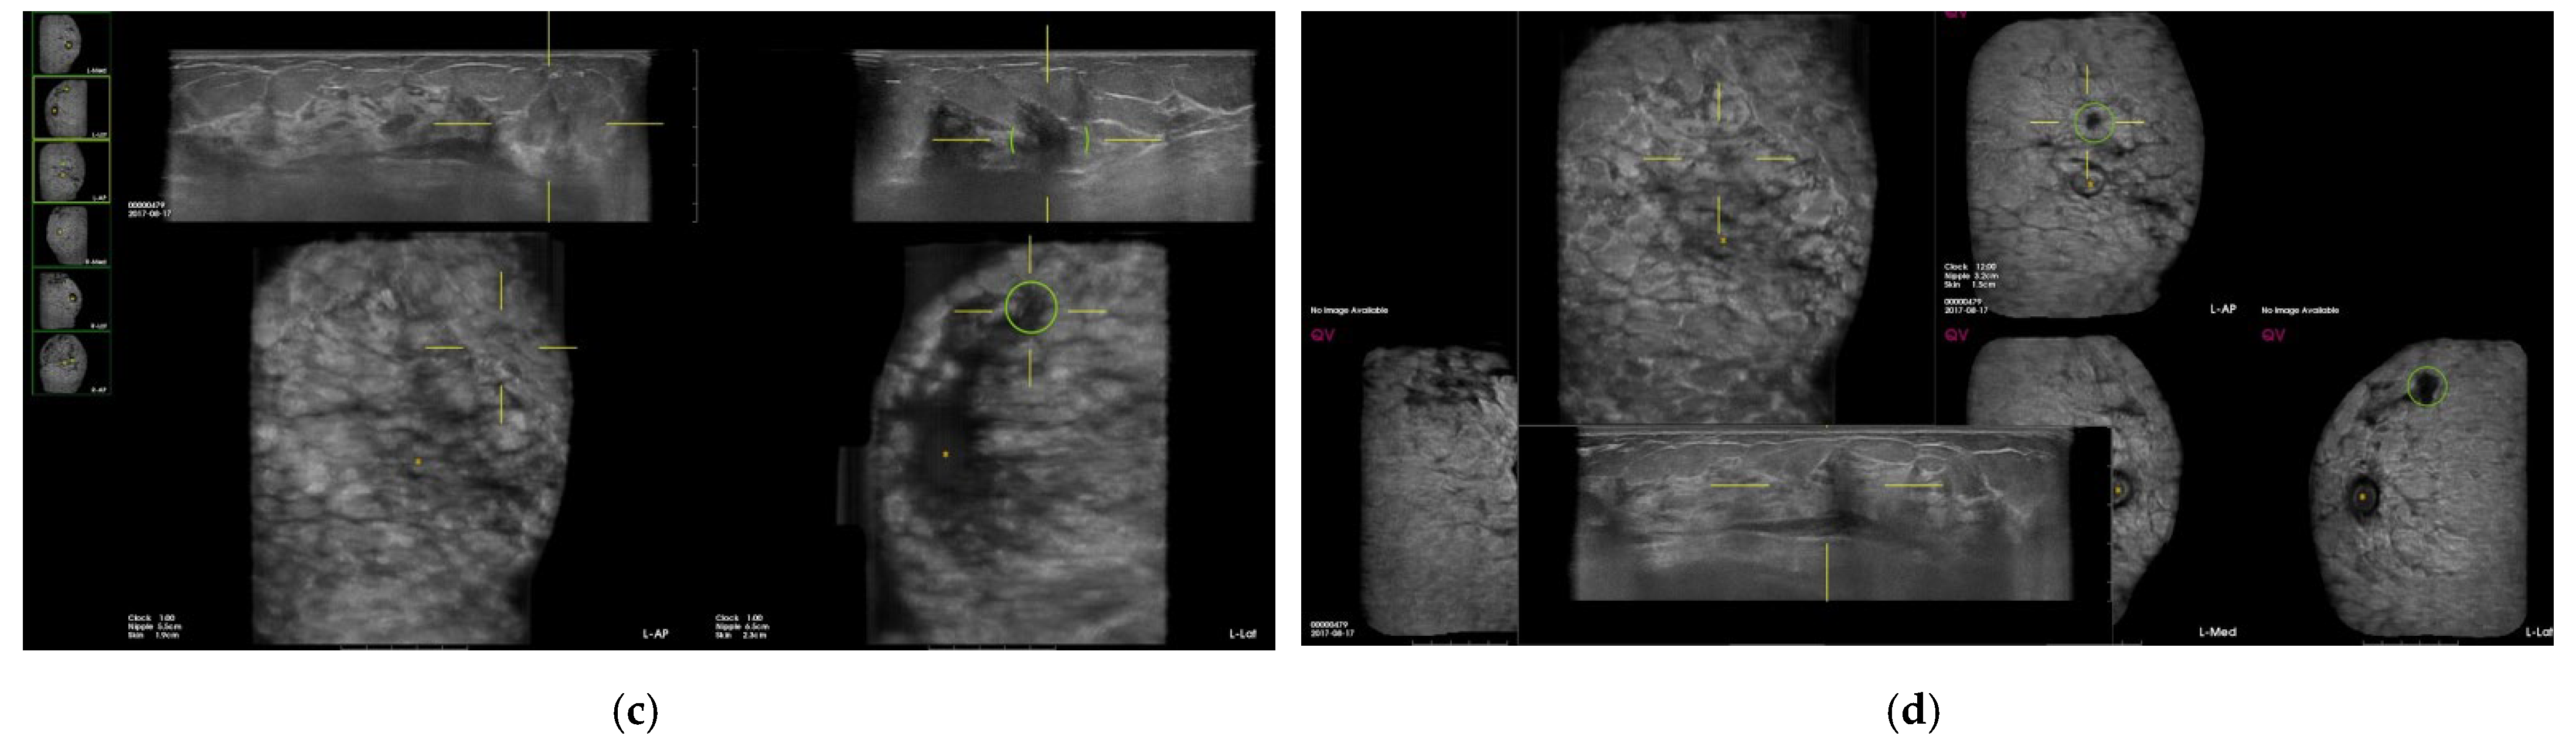

| False-positive marks for pseudolesions | 459 | 86 |

| Marginal shadowing | 209 | 39.1 |

| Cooper’s ligament shadowing | 143 | 26.8 |

| Periareolar shadowing | 64 | 12 |

| Rib | 37 | 6.9 |

| Skin lesion | 6 | 1.1 |